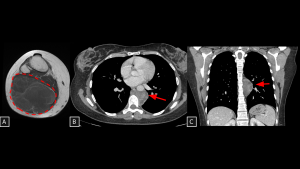

Fig 20: Case 21 – Paravertebral mediastinal metastasis:

A 35-year-old patient with an atypical lipomatous tumor of the right leg (previously operated, with local recurrence demonstrated on MRI (A) developed a heterogeneous solid lesion in the paravertebral mediastinum (arrow in B). The lesion was located anterior and left to the thoracic vertebral bodies and contained foci of fat attenuation (arrows in B and C), consistent with secondary involvement.

SYSTEMATIC APPROACH: 1. Age: Adults / Elderly (History of primary malignancy). | 2. Morphology: Osteolytic bone destruction or conglomerate nodal mass. | 3. Enhancement: Variable (depends on primary). | 4. Relevant Anatomical Relationships: Destroys vertebral body or invades adjacent organs.